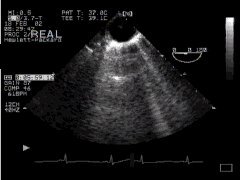

If we wish, we can view the aorta in long axis by rotating the biplane or multiplane probe through ninety degrees - 'DESC Aorta LAX':

CLICK FOR VIDEO: descending aorta lax view

MPG  MPG4  QT  Real